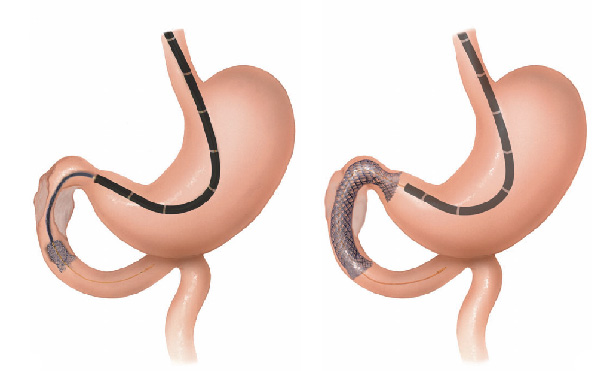

Estenose do intestino

Estenose do intestino é o estreitamento parcial ou total do intestino grosso (ou raramente do intestino delgado) que impede a progressão do conteúdo através do mesmo.

Estenose do intestino pode acontecer por 2 causas principais:

1- Tumores do intestino: alguns tumores do intestino podem crescer ao ponto de causar a obstrução do órgão. Nestes casos geralmente realiza-se cirurgia para se retirar a parte do intestino acometida. Nos casos muito avançados pode-se passar através da colonoscopia uma prótese autoexpansível para desobstrução. Esta prótese também pode ser colocada para melhorar o estado físico e o preparo do paciente antes de ser realizado uma cirurgia definitiva.

2- Estenose benigna: algumas inflamações do intestino podem ao cicatrizar levar a retração da parede do órgão e fechamento do mesmo. Doenças como a Retocolite Ulcerativa, a Doença de Crohn, a Colite por radioterapia, e algumas infecções do intestino podem levar a este processo. Existem também as estenoses pós operatórias que acontecem quando ocorre uma cicatrização exagerada da parede do intestino remanescente após a cirurgia.

Nos casos de estenoses benignas do intestino realiza-se a dilatação endoscópica da região com balão do tipo hidrostático.

Estenose do intestino

Estenose do intestino é o estreitamento parcial ou total do intestino grosso (ou raramente do intestino delgado) que impede a progressão do conteúdo através do mesmo.

Estenose do intestino pode acontecer por 2 causas principais:

1- Tumores do intestino: alguns tumores do intestino podem crescer ao ponto de causar a obstrução do órgão. Nestes casos geralmente realiza-se cirurgia para se retirar a parte do intestino acometida. Nos casos muito avançados pode-se passar através da colonoscopia uma prótese autoexpansível para desobstrução. Esta prótese também pode ser colocada para melhorar o estado físico e o preparo do paciente antes de ser realizado uma cirurgia definitiva.

2- Estenose benigna: algumas inflamações do intestino podem ao cicatrizar levar a retração da parede do órgão e fechamento do mesmo. Doenças como a Retocolite Ulcerativa, a Doença de Crohn, a Colite por radioterapia, e algumas infecções do intestino podem levar a este processo. Existem também as estenoses pós operatórias que acontecem quando ocorre uma cicatrização exagerada da parede do intestino remanescente após a cirurgia.

Nos casos de estenoses benignas do intestino realiza-se a dilatação endoscópica da região com balão do tipo hidrostático.